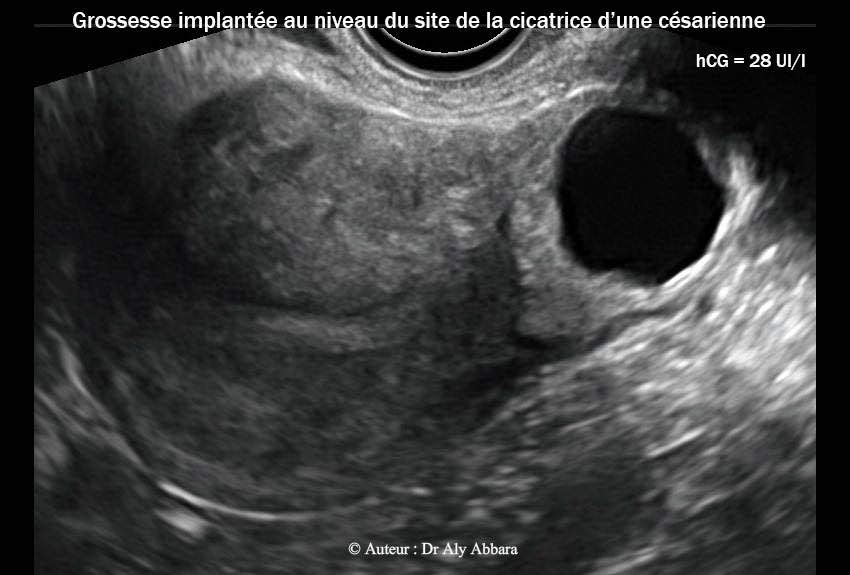

• Images échographiques par voie endovaginale montrant un sac gestationnel d'une grossesse débutante et partiellement intramurale, implantée dans le site de la cicatrice de l'hystérotomie segmentaire transversale d'une ancienne césarienne.

• L'aspect du sac gestationnel au 15e semaine post traitement médical par méthotrexate : il mesure 25 x 24 x 20 mm de diamètres (= 6,2 cm3) ; le dosage de β-hCG plasmatique était égal à 28 UI/l.

17.01.2013 = (J105) = 15 S 28 UI/l 25 x 24 x 20 mm = 6,2 cm3 J0